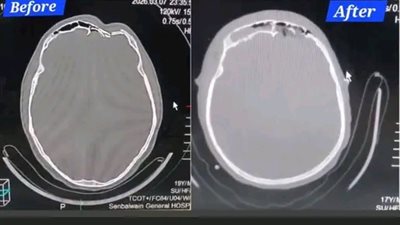

إنقاذ مريض من كسر معقد بعظام الجبهة والوجه بمستشفى السنبلاوين العام